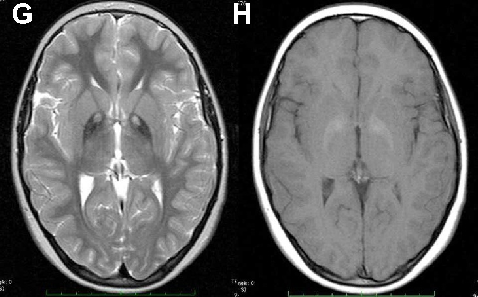

Pantothenate kinase-associated Neurodegeneration

PKAN is an autosomal recessive condition included in the group of disorders known as neurodegeneration with brain iron accumulation (NBIA). PKAN is the only NBIA in which acanthocytosis has been reported so far, and typically presents in childhood with rapid progression over 10 years (Table 2) [12]. Initial manifestations include orofacial and limb dystonia, choreoathetosis and spasticity. Lingual dystonia can be prominent, but is not specifically related to eating as in ChAc. Other speech difficulties specifically palilalia or dysarthria, are prominent features of PKAN [12]. Most patients develop pigmentary retinopathy and one third cognitive impairment. About 8 to 10% of PKAN patients have acanthocytosis, perhaps due to abnormalities of lipid synthesis [12]. Onset can be later, with more rigidity in atypical forms of PKAN [12], but the typical MRI findings of the “eye of the tiger” sign suggest the diagnosis.

In ChAc and MLS, electroneurography may demonstrate sensorimotor axonal neuropathy whereas electromyography may show neurogenic as well as myopathic alterations. Electroencephalographic findings are not specific and may comprise normal findings, generalized slowing, focal slowing, and epileptiform discharges. Neuroradiologically, there is progressive striatal atrophy especially affecting the head of caudate nucleus and impaired striatal glucose metabolism similar to that seen in HD (Figure 2) [24,26]. Voxel-based morphometry of MRI scans in ChAc shows specific involvement of the head of the caudate nucleus [41,42]. Neurodegeneration in both core NA syndromes affects predominantly the caudate nucleus, putamen and globus pallidus. In ChAc, thalamus and substantia nigra are also involved. In contrast to HD, there is no significant cortical pathology [8,43-45]. Neuropathological findings consist of neuronal loss and gliosis of variable degree in these regions, but no inclusion bodies of any nature or other distinct neuropathological features have as yet been detected.

Cerebral MRI is often diagnostic in PKAN, and the diagnosis is confirmed by analysis of the PANK2 gene (Figure 2). Analysis of the JPH3 gene CTG expansion is useful in patients of African ancestry with suspected HDL2.

A B

C D

E F

G H

Figure 2 Neuroimaging. ChAc. Coronal FLAIR- (A) and axial T1-weighted (B) images demonstrate moderate atrophy of the caudate nucleus. MLS. Axial T2-weighted images demonstrate moderate atrophy of caudate nucleus and putamen (C) but no relevant cortical atrophy (D). HDL2. Axial FLAIR- (E) and coronal T1-weighted images (F) demonstrate atrophy of the caudate nucleus and the fronto-temporal cortex. In addition, FLAIR images show periventricular white matter hyperintensities (courtesy of Nora Chan, MD, UCLA, Los Angeles, USA). PKAN. T2-weighted fast spin echo (G) and T1-weighted (H) brain MRI scans from a child with PKAN demonstrating the “eye of the tiger” sign (courtesy of Susan J. Hayflick, MD, Oregon Health and Science University, Portland, Oregon, USA)